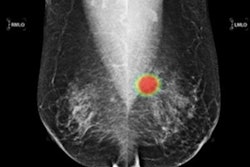

Of particular note will be a study the company conducted with the Japan National Cancer Center East (NCCE), which investigated microsatellite stable locally advanced rectal cancer with the firm's Lunit SCOPE IO, an AI-powered tumor-infiltrating lymphocyte (TIL) analyzer.

The research measured tumor-infiltrating lymphocyte density during chemoradiotherapy and found a link between the change in TIL density and the pathologic complete response rate, according to Lunit.